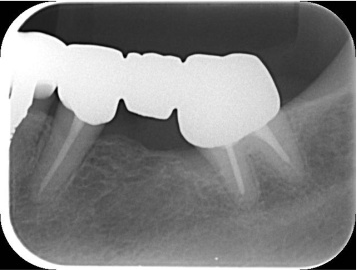

デンタル10枚法及びプロービングチャート

デンタル10枚法及びプロービングチャートです。

全体的には歯槽骨の吸収はみられませんが、左下7は左下8の影響により、遠心部に垂直性の骨欠損がみられます。

右上2から左上1には不十分な根管充填がみられます。

根管治療終了時口腔内写真およびレントゲン写真

根管治療終了時のレントゲン写真及び口腔内写真です。右上1番の根尖病巣の縮小がみられるため、保存可能と判断し矯正治療を行うことにしました。

矯正的挺出終了時の口腔内写真及びデンタル

矯正的挺出終了時の口腔内写真及びデンタル写真です。

レントゲン上で目標とする挺出量がかくとくできたので、この段階で歯周形成外科を行うことにしました。